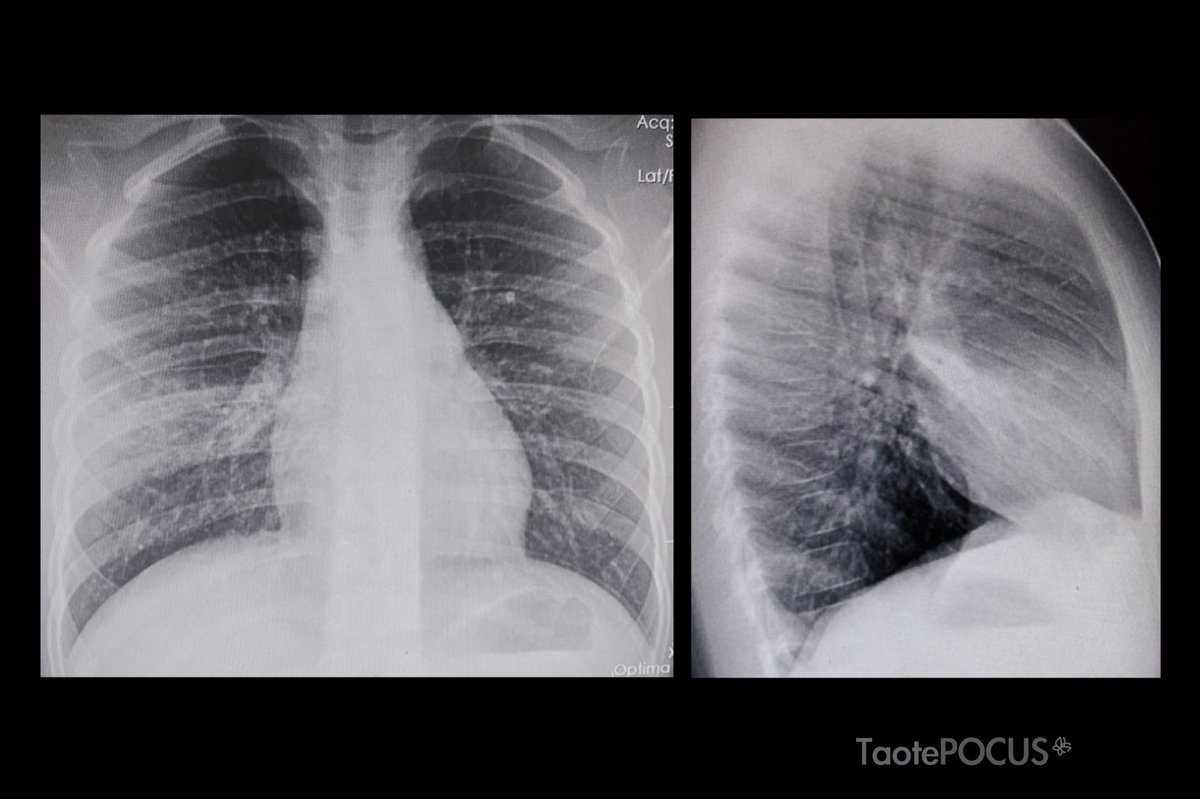

7 y/o ๐Ÿง’๐Ÿป

1 day with dry cough + fever

Normal ๐Ÿซ๐Ÿฉบ

X ray